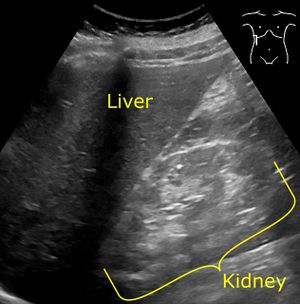

يُنصح مرضى السكري بفحص مستويات الألبومين سنويًا ، بدءًا فور تشخيص مرض السكري من النمط 2 وبعد خمس سنوات من تشخيص مرض السكري من النمط 1.[24][27] يوصى بالتصوير الطبي للكلى ، بشكل عام عن طريق تخطيط الصدي ، كجزء من التشخيص التفريقي إذا كان هناك اشتباه في انسداد المسالك البولية أو عدوى المسالك البولية أو حصوات الكلى أو مرض الكلى المتعدد الكيسات.[28] يجب إجراء خزعة الكلى فقط في حالة الاشتباه في مرض الكلى غير السكري.